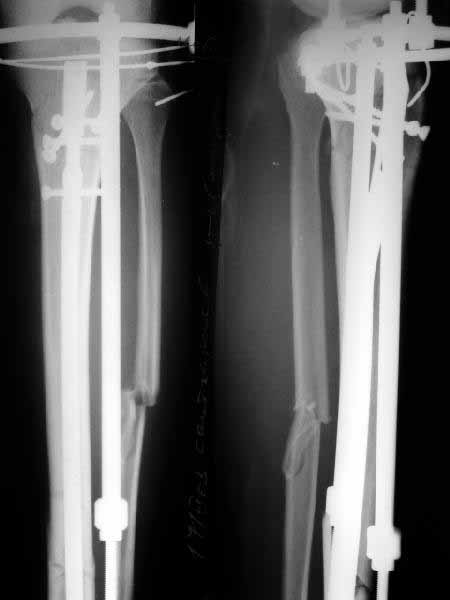

![]() |

If you were to look at the X ray picture, the fracture comes close to the junction of upper one third with lower two third. In this anatomical location the AO design nail tends, not to allow an anatomical reduction and in fact may push the distal fragment to posterior displacement and distraction to an unacceptable extent.

Any comments from any hardline AO group members?????.

DTIG> You asked why the AO design with the low Herzog curve is unsuited for this junction of upper one third with lower two third. In this anatomical location the AO design nail tends, not to allow an anatomical reduction and in fact may push the distal fragment to posterior

It still can be performed. IMHO the only limitation is that the proximal fragment must be have enough space for at least two screws.

See a recent example in a 76 y.o. female.